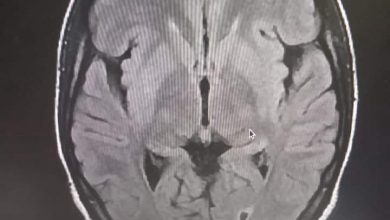

المستشفى العسكري ينجح في إجراء أول عملية تفتيت جلطة دماغية في موريتانيا

تمكن فريق طبي متخصص بالمستشفى العسكري بنواكشوط، من تفتيت جلطة دماغية لمريضة في العشرينيات من العمر، بعد وصولها في حالة…